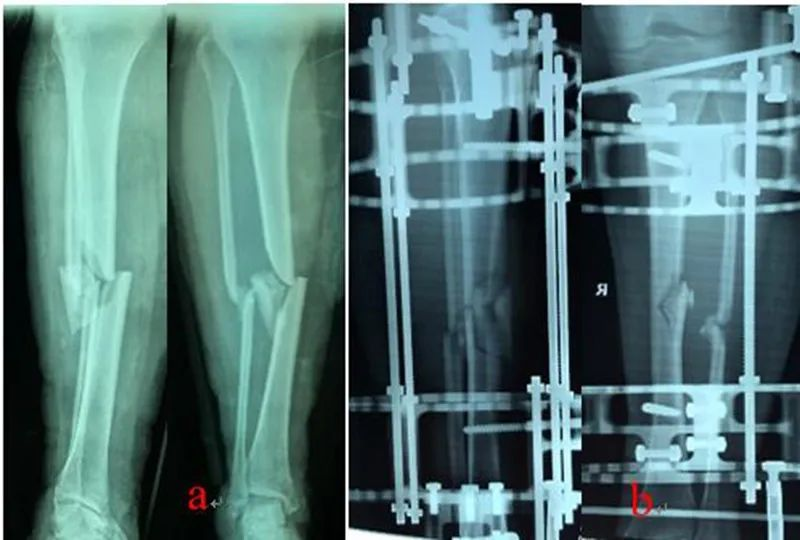

利用骨科外固定架(QF)和数字六轴外架(QSF)治疗胫骨骨折,获得良好的临床疗效.骨科外固定架具有自动复位骨折功能,4根螺纹连接杆与骨的轴线平行,通过旋拧调节螺母,调节两个固定环之间的距离,实现对骨折断端轴向应力的调节和固定方式的转换,早期坚强固定,中期加压固定,后期弹性固定。复位过程无需透视,不依赖医生经验,手术时间短,可以不用麻醉,术后即可完全负重下地行走,复位精确,固定合理,操作简便。数字六轴外架QSF配套软件基于CT数据,与国际同类产品比较,复位精确,固定牢靠,操作简便,学习曲线短。

图1:QF治疗胫腓骨骨折